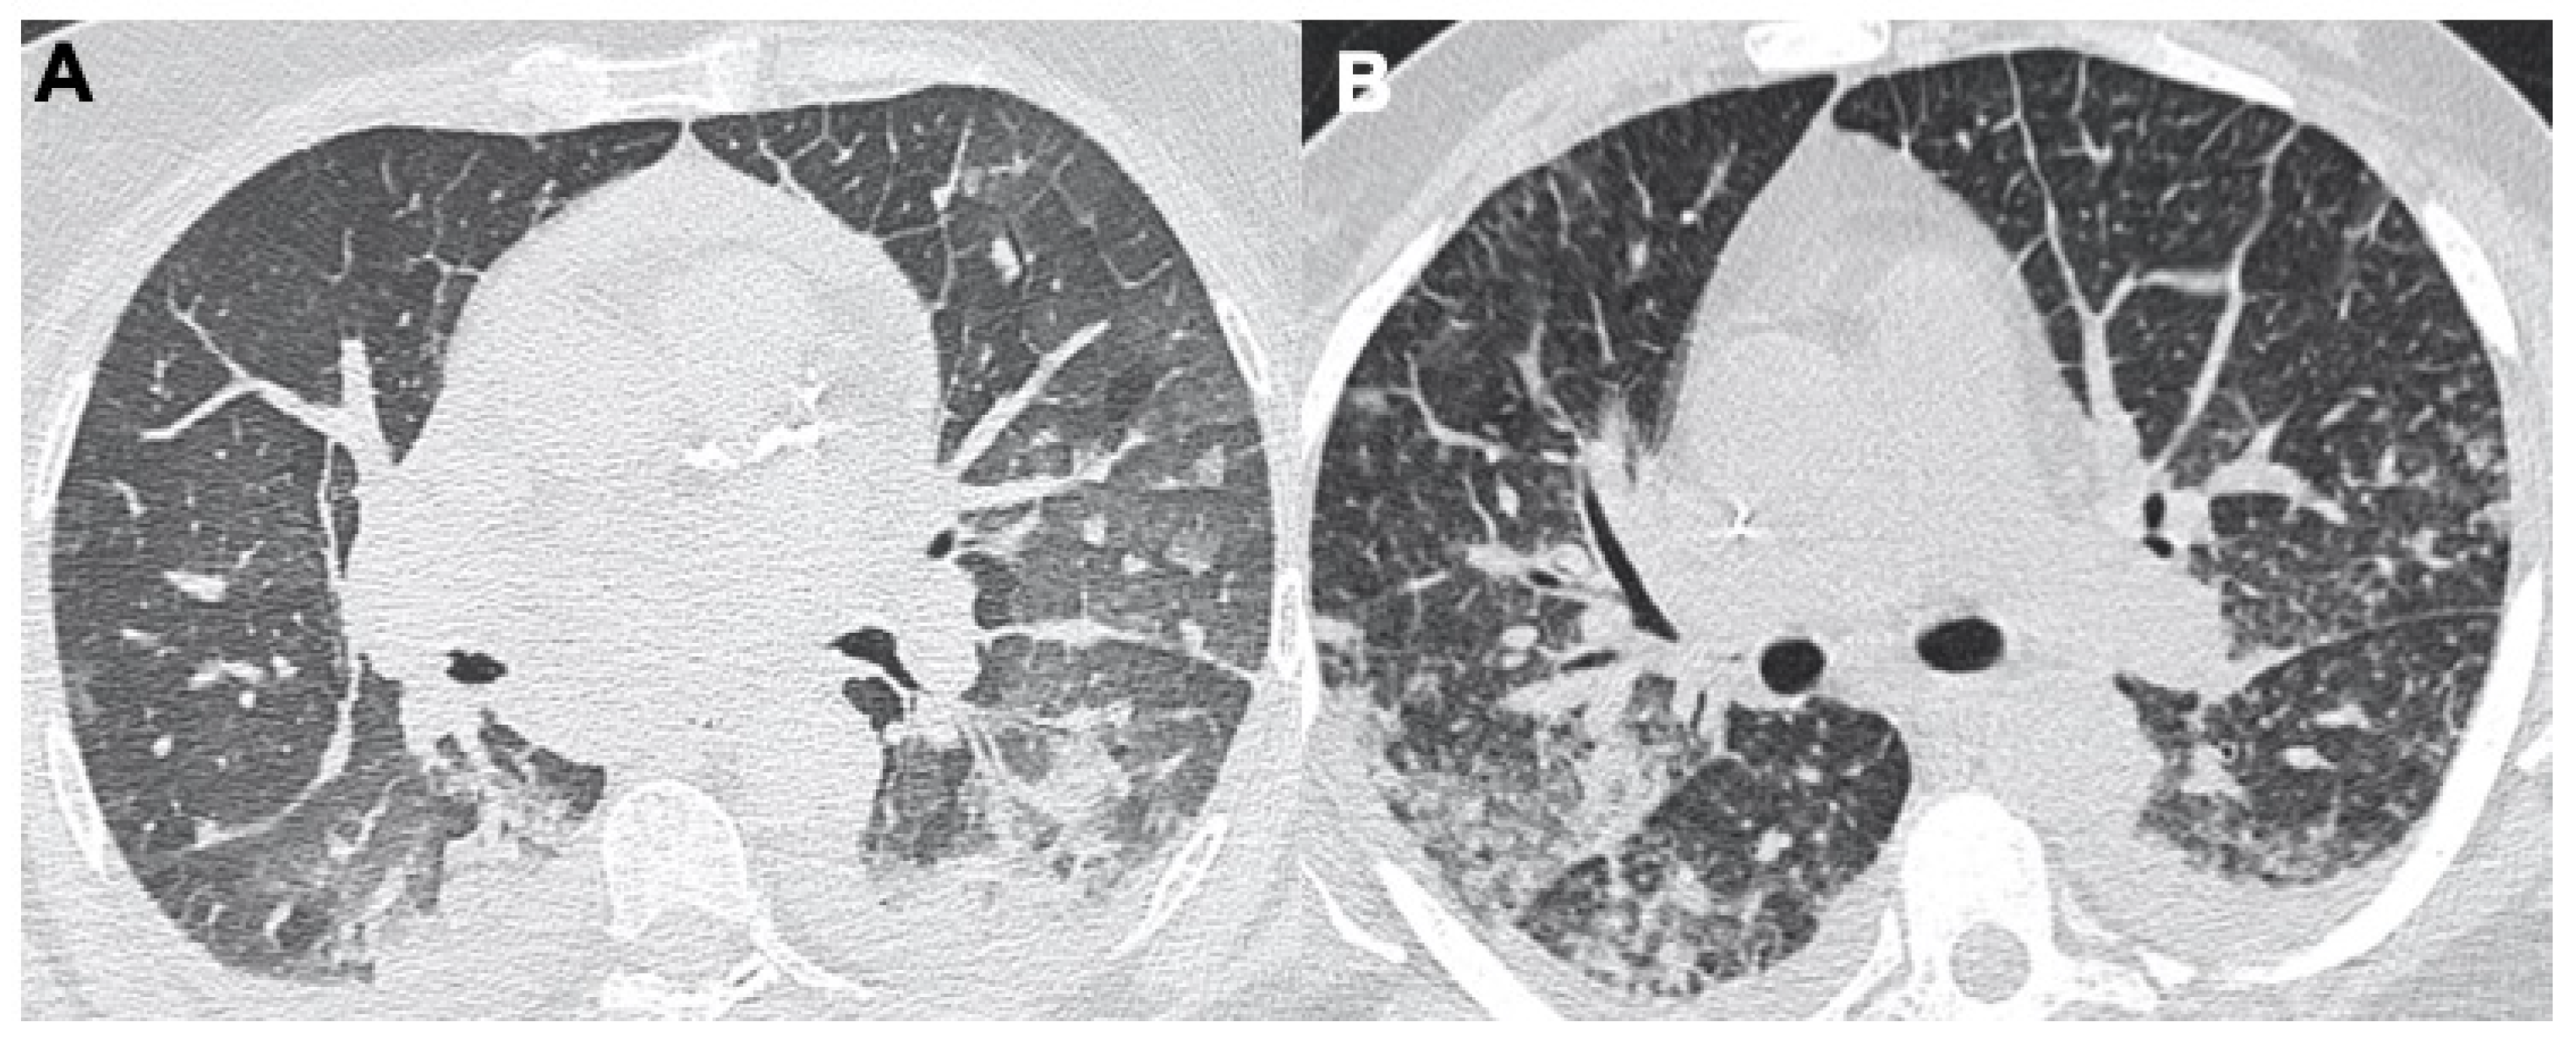

2.3. Pulmonary Embolism